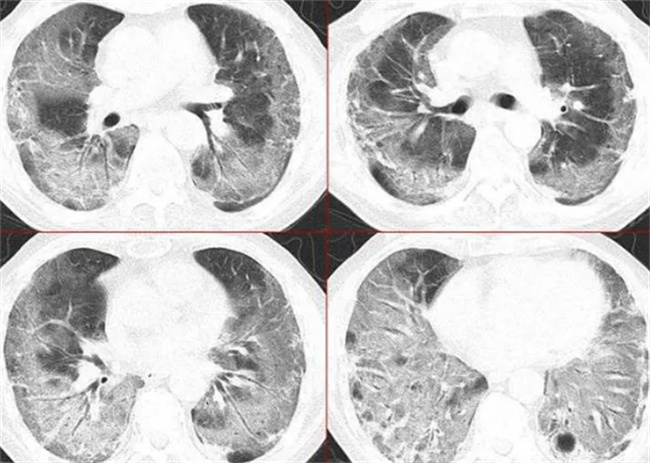

白肺并不是肺部变白,而是影像学上的一个术语。在胸部CT还有胸片拍摄时,肺部的影像学可能会出现黑色,如果颜色变白这就是一种密度变稠的表现。

就是影像学上的一个术语,在拍摄CT之后就会发现肺部影像学主要表现的就是黑色,如果颜色变白,这就意味着密度增稠。大叶性肺炎时还会出现出一种片状变白,会沿着支气管分布。一般在2~3天内就会变成大片的白色状阴影,在临床上会被称之为大白肺,很容易就会引起呼吸衰竭,还有急性呼吸窘迫综合症。

三、如何确定白肺